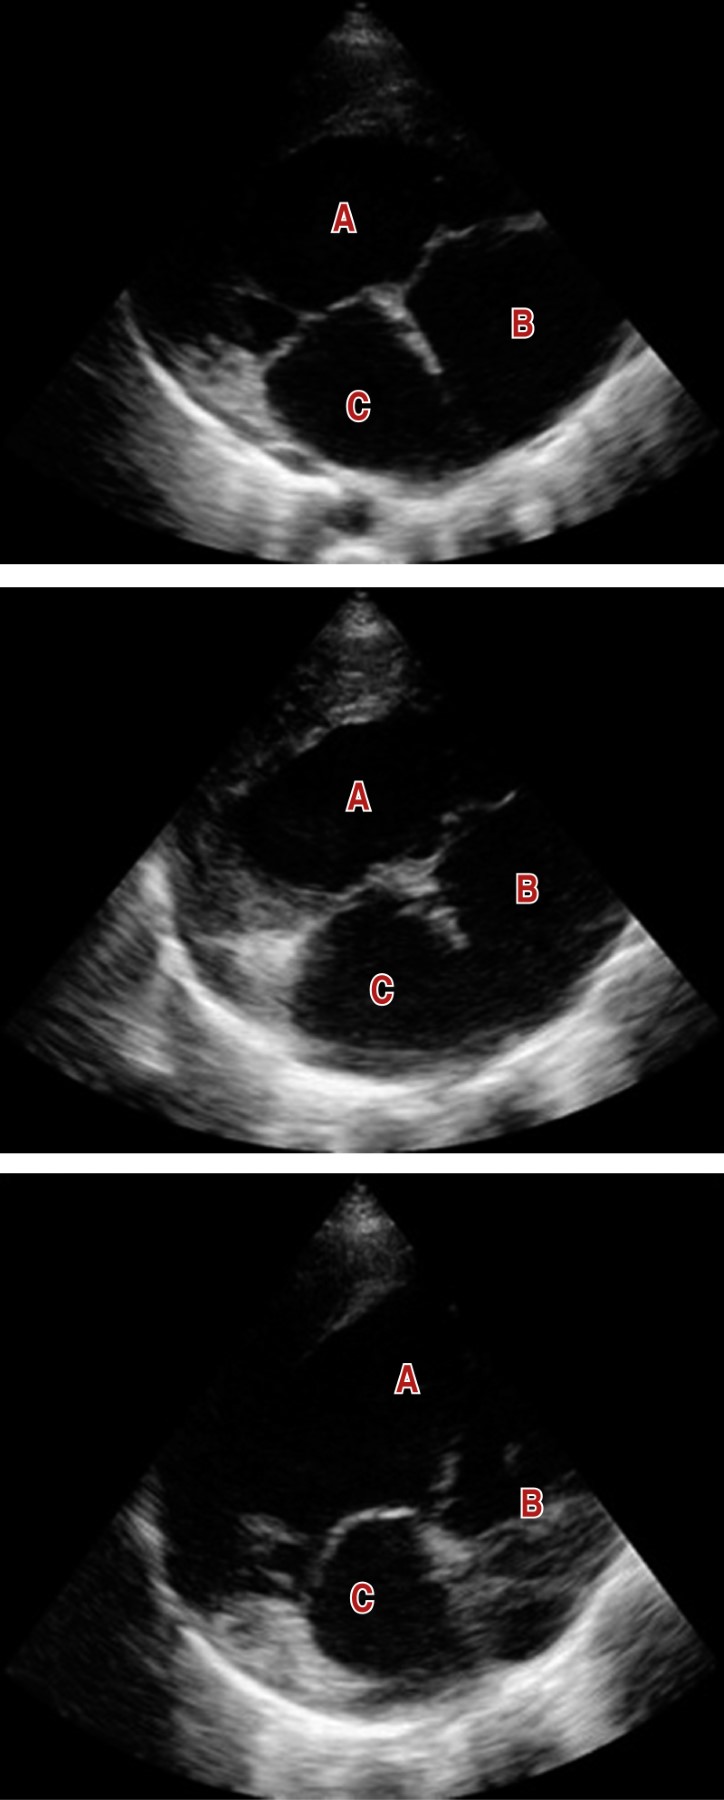

Ventrículo único en adulto de 28 años de edad, historia y actualidad de un corazón no quirúrgico

Herrera-Morales JA, Becerra-Gutiérrez CA, Cazares-Hernández KE, Palomares-Alonso VI

Introducción: el ventrículo único es una patología poco frecuente dentro de las cardiopatías congénitas en el adulto. Este es un grupo de anomalías graves de la estructura del corazón tras un mal desarrollo, que da como resultado una sola cámara ventricular. En esta población las medidas farmacológicas son poco eficaces para evitar la progresión de una falla cardiaca terminal; sin embargo, existen procedimientos quirúrgicos que ayudan a alargar la supervivencia y la calidad de vida. Objetivo: reportar el caso de una cardiopatía congénita en el adulto de baja prevalencia. Caso clínico: se presenta el caso de un hombre de 28 años con antecedente de cardiopatía congénita cianógena de tipo corazón univentricular de morfología indeterminada con doble vía de salida diagnosticada desde su primer año de vida, que ha llevado solamente manejo médico. Conclusiones: desafortunadamente, al ser una cardiopatía congénita poco frecuente en los adultos, existen pocas referencias sobre su manejo médico. Si no son sometidos a intervención quirúrgica en edades tempranas, lo que ofrece mayor calidad de vida y supervivencia, algunos pacientes fallecen durante la lactancia debido a insuficiencia cardiaca.

Figura 1